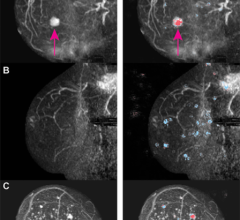

Despite decades of progress in breast imaging, one challenge continues to test even the most skilled radiologists ...